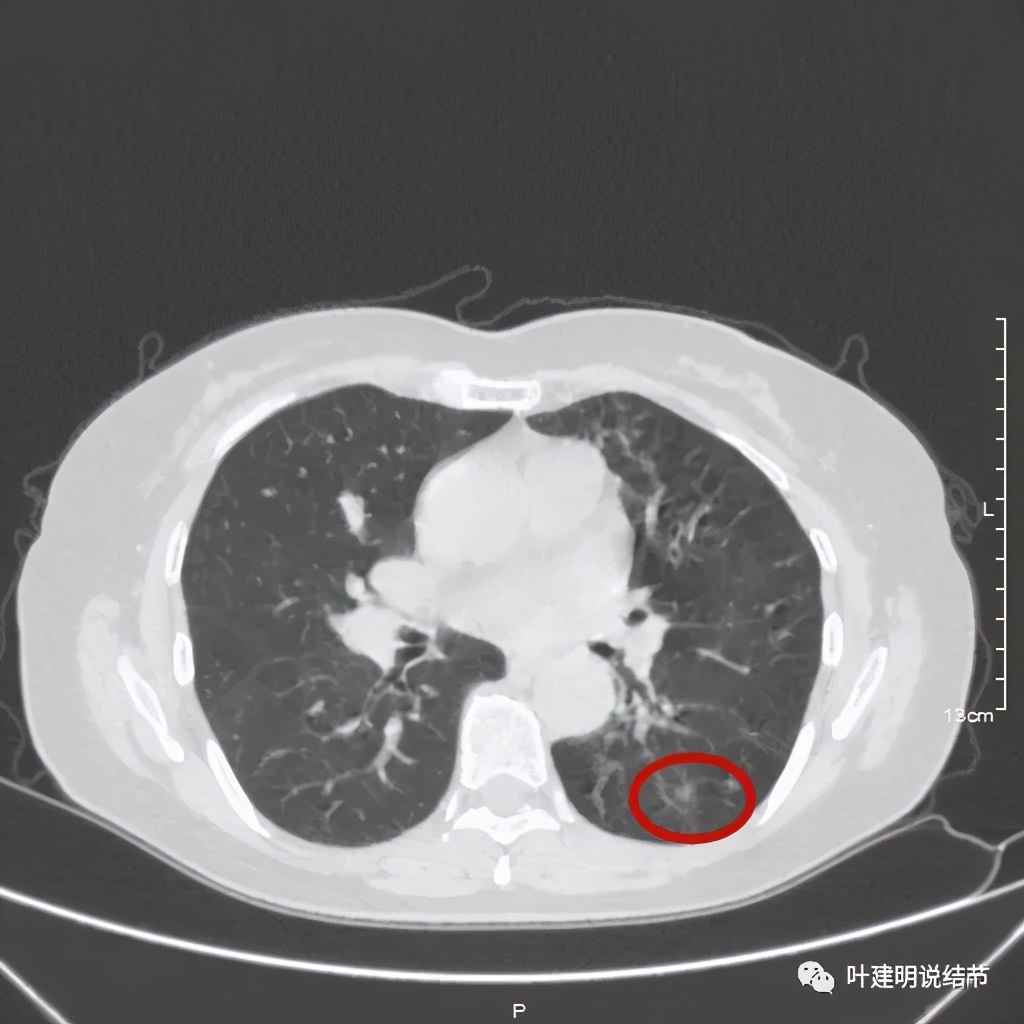

金华的某A,女性,56岁,去年8月份检查发现左肺下叶结节,是实性的,还中间有个空洞,我们说若磨玻璃结节伴空泡或空腔多为恶性范畴的,实性的也是可能性会大一些,但不如磨玻璃确切,因为结核、感染等也会类似的。我们先来看她当时的CT图像:

左下结节与血管关系密切,此层似磨玻璃结节,还夹在小血管之间,其中有血管紧贴病灶,略迂曲